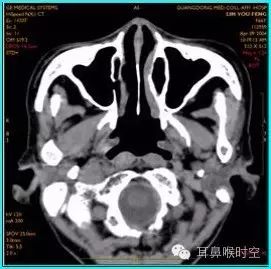

C T— computed tomography

咽部正常CT表现

(1)鼻咽腔层面:

CT检查扫描方法

①鼻咽部轴扫:常规OML (听眦线)

扫描体位:标准仰卧头颅正位

扫描参数:OML基线,层厚3mm/5mm,螺距1.0。

扫描范围:以侧位作为定位线,包括中耳乳突进行螺旋方式扫描

部分进行静脉增强扫描;

CT 观察与测量方法

①标准CT 轴位:主要观察12项结构

鼻咽腔的形态

腺样体大小与形态

咽隐窝

咽鼓管咽口

圆枕

鼻后孔的阻塞情况

翼内外板

翼内外肌

咽旁间隙

邻近骨质有无破坏

鼻旁窦

中耳乳突等。

标准CT 轴位像:

鼻咽气腔形态因层面不同而不同,其中,呈梯形(图3),长方形(图4)。

咽隐窝及咽鼓管咽口清晰或隐约可见,双侧对称,鼻后孔大部分畅通,咽旁间隙清晰,邻近骨质无破坏。